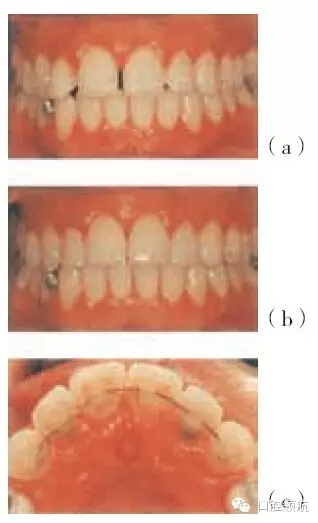

圖29.9 (a)慢性牙周病的成年女性患者,在牙周治療及正畸之前上中切牙移位。(b)治療后。(c)固定正畸保持器

圖29.10 (a~c)33歲的侵襲性牙周炎女性患者,牙周治療前左上中切牙的移位及前傾反復(fù)牙周膿腫,若不進(jìn)行牙周治療則牙齒預(yù)后不好,應(yīng)患者要求,正畸治療采用活動(dòng)矯治器

圖29.11 圖29.10中的患者正畸治療之后的圖片,牙縫已關(guān)閉。(a)固定保持器。(b)6年后,牙周及正畸聯(lián)合治療效果的穩(wěn)定性。